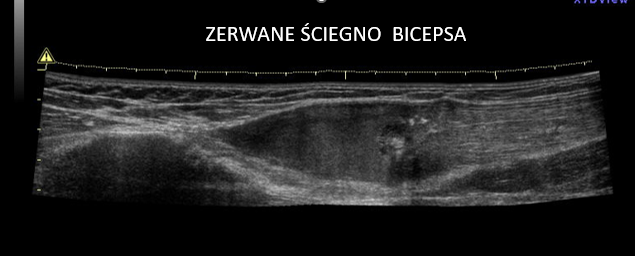

7. Patologie ścięgna bicepsa

Ścięgno głowy długiej mięśnia dwugłowego ramienia jest częstym źródłem bólu.

USG wykrywa:

- przemieszczenie ścięgna

- zapalenie (tenosynovitis)

- zerwania